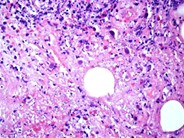

Herpes simplex lymphadenitis - 2.

Herpes simplex lymphadenitis - 2. from imagebank.hematology.org